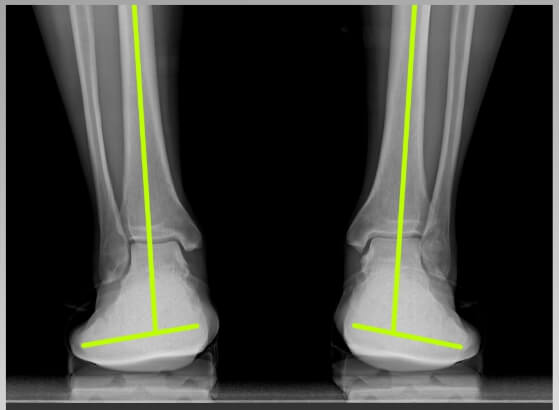

보통 푹신한 신발이 편할 것 같지만 오래 신으면 오히려 발 아치가 무너져 체중을 지탱할 때 발이 쉽게 피로해지고 관절, 근육, 인대에 무리를 준다고 합니다. 하지만 골 스튜디오 그래비티 밸러스의 단단한 미드솔은 아치가 지지 않도록 받쳐주어서 발과 무릎 골반의 부담을 감소시키며 발 피로해소에 도움을 줍니다. 부드러운 아웃솔의 쿠션감이 체중의 2배~ 2배에 달하는 하중과 지면의 충격이 발과 관절에 전달되지 않게 완충하는 역할을 합니다.